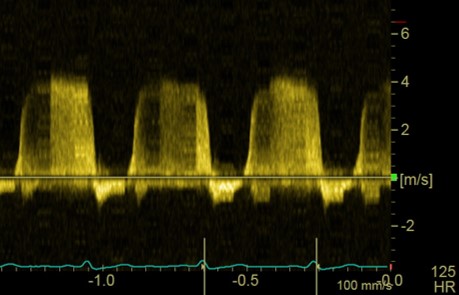

Chaque participant présente un cas clinique (ou plusieurs images) pour revoir le protocole d'échocardiographie et échanger :

Le formateur proposera également quelques coupes échocardiographique non conventionnelles et quelques cas “pièges” pour approfondir l'analyse et la réflexion.